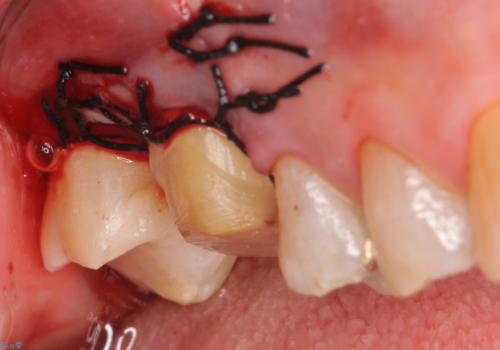

右上6,7の金歯を外したところ、虫歯が歯茎より深い位置まで進行していたため歯周外科を行いました。

その後歯茎の回復を待ち、オールセラミッククラウンおよびセラミックインレーによる補綴・修復を行いました。